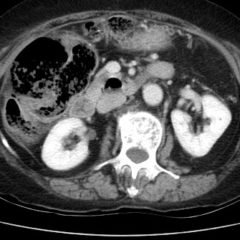

Point-of-care cardiac echocardiogram demonstrated a dilated ascending aorta (illustrated in red) measuring approximately 4 cm in the parasternal long axis (PLAX). A dilated aortic arch (illustrated in green) also measuring approximately 4 cm was appreciated using the suprasternal notch view (SSNV). A follow-up computed tomography angiogram (CTA) was performed, validating bedside ultrasound measurements.

The diagnostic criteria for dilated thoracic aneurysm is based on multiple factors including age, sex, and body size.2 An aortic root diameter of ³ 4.0 cm constitutes an ascending aortic dilation.3,4 Point-of-care cardiac and SSNV ultrasound of the thoracic aorta has been validated as an accurate study when performed by emergency physicians to identify thoracic aortic aneurysms (sensitivity of 71.4%, specificity of 100% when compared to gold standard of CTA). 5 This case is an example of the utility of rapid bedside diagnostic ultrasound, specifically the SSNV, in assessment of thoracic aneurysms.